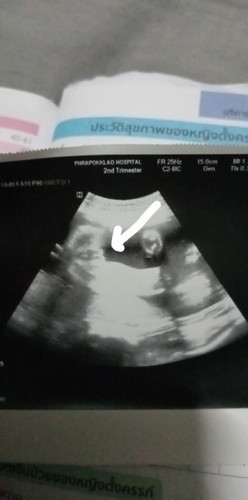

อันนี้ใช่จิ๊น้องมั้ยคะ หมอบอกน่าจะผญ.แต่แม่ยังไม่กล้าเชื่อเลยค่ะ ซาวตอน26วีค

น่าจะหญิงค่ะแม่มีกลีบ